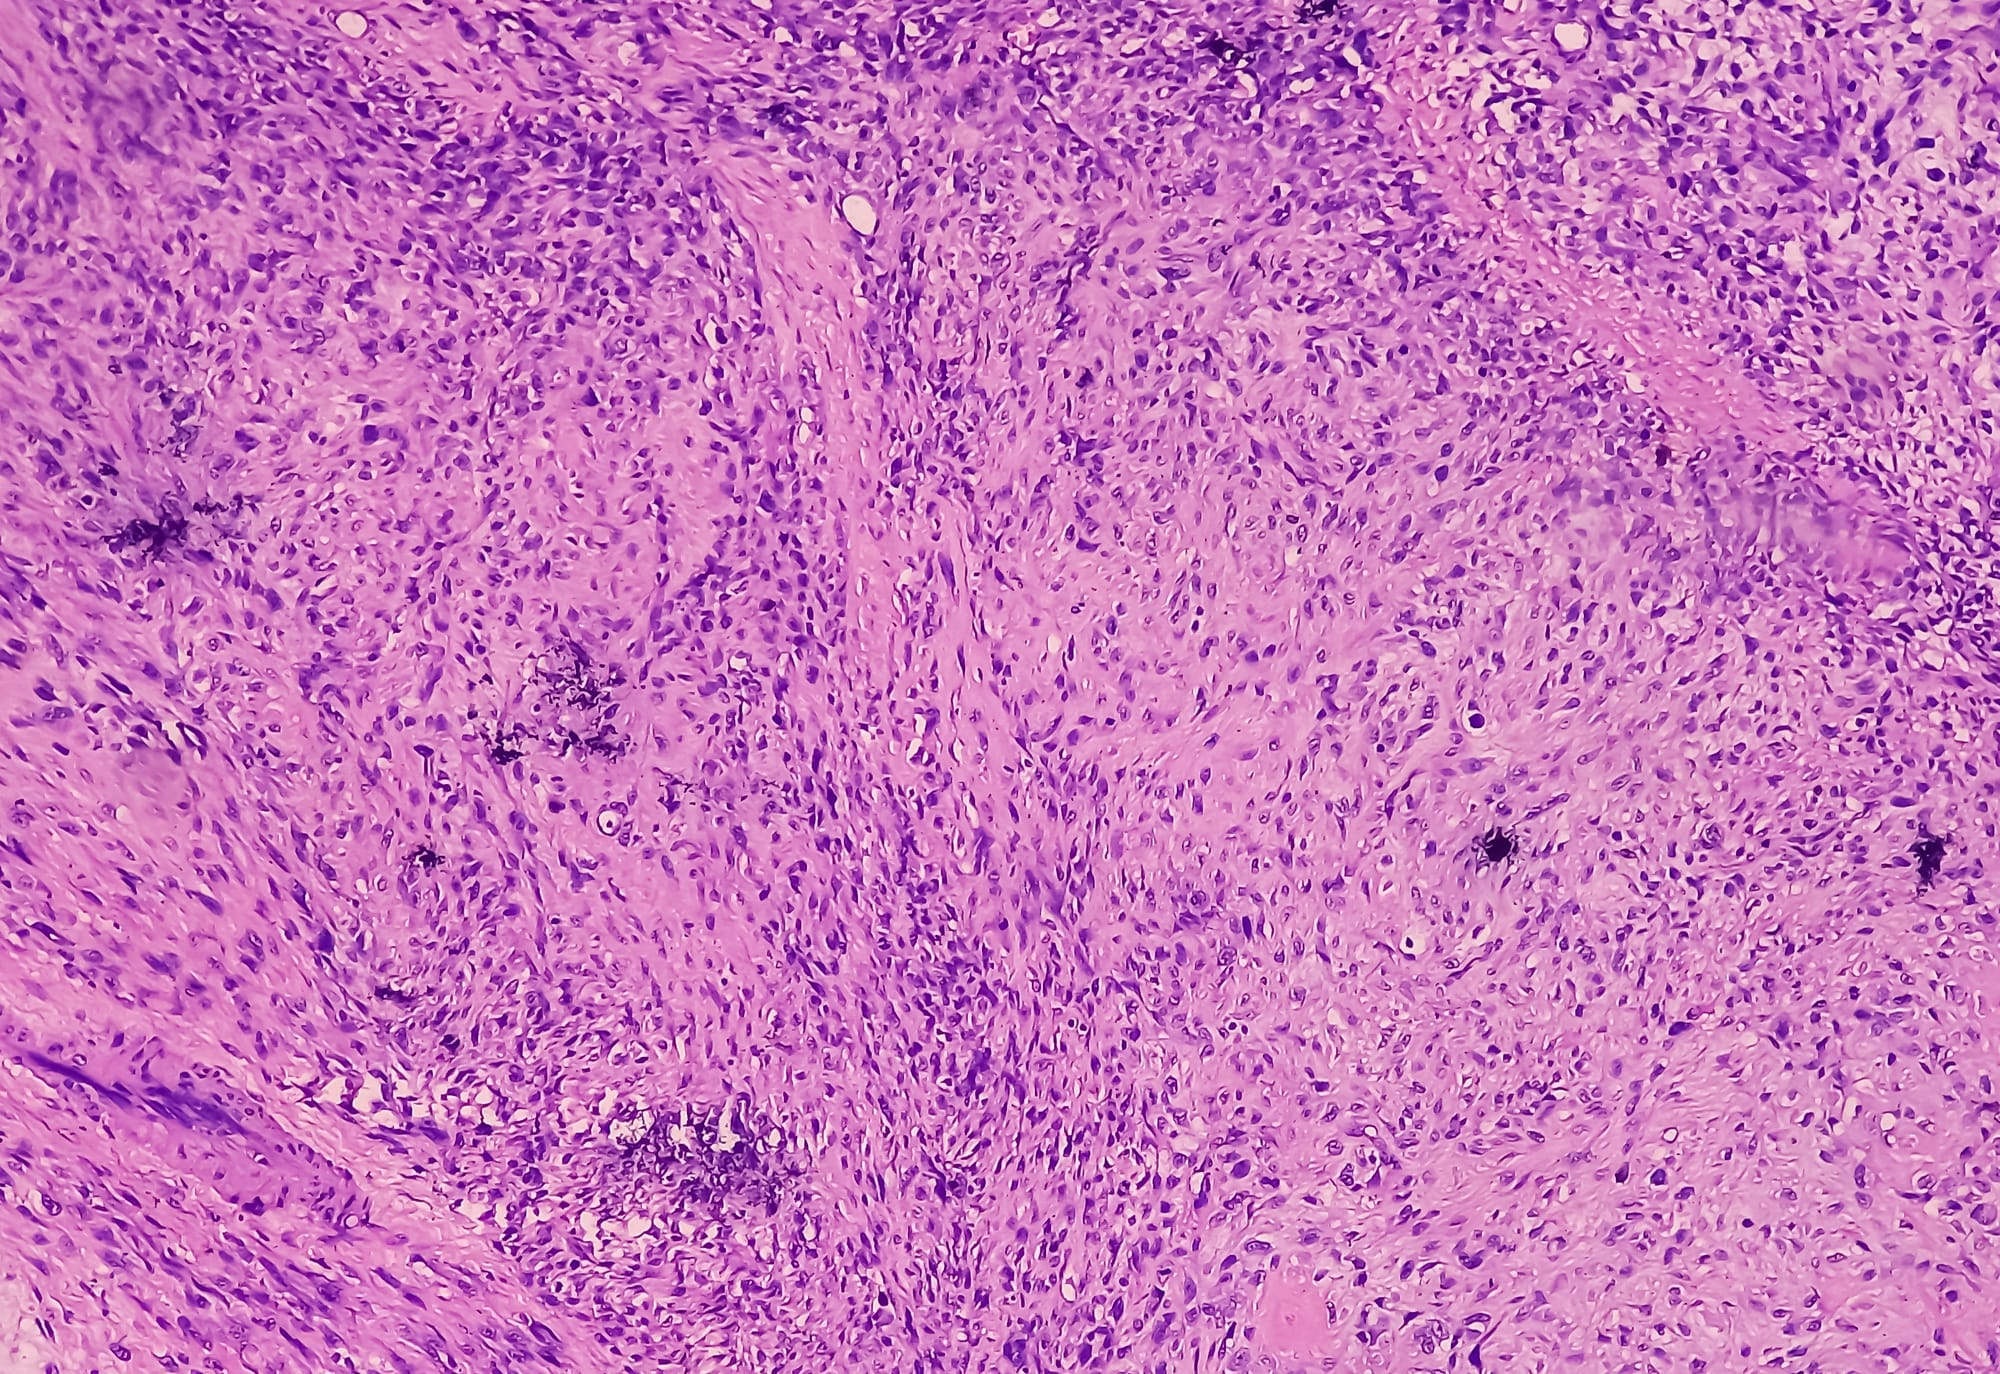

Low-grade fibromyxoid sarcoma (LGFMS) is a rare fibroblastic neoplasm with an indolent clinical course. It is a distinctive subclass of soft tissue sarcoma with metastasizing potential and sometimes a long interval between tumor presentation and metastasis. This case report describes a 60-year-old female with an unresectable pleural LGFMS initially misdiagnosed as malignant mesothelioma. Pleural LGFMS remains exceedingly rare, with only four prior cases reported. Given its histologically benign appearance, LGFMS poses diagnostic challenges and risks of local recurrence or metastasis. This case underscores the importance of accurate diagnosis using MUC4 and it explores endocrine therapy as a promising palliative option for unresectable LGFMS, contributing valuable insights into management strategies for this rare entity.